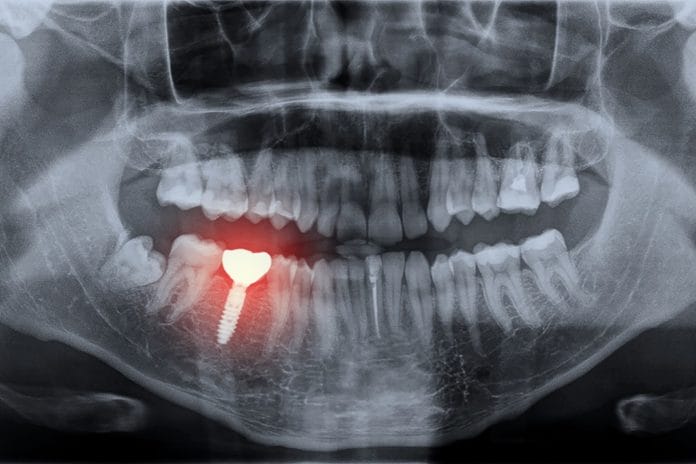

Implant dentistry has improved the quality of life for much of the world. Regardless of how technology has advanced, peri-implant disease remains a global concern with an emphasis on maintenance.

Restorations supported by dental implants are designed to resemble a natural dentition. However, professional and at-home maintenance methods should be tailored to the design of the supporting restoration (and patient), not teeth! Coincidentally, the design of the restoration can be the major component causing the problem. Either way, it is the role of the dental hygienist to identify risk factors for disease, intervene when it is detected, and prevent it from happening!